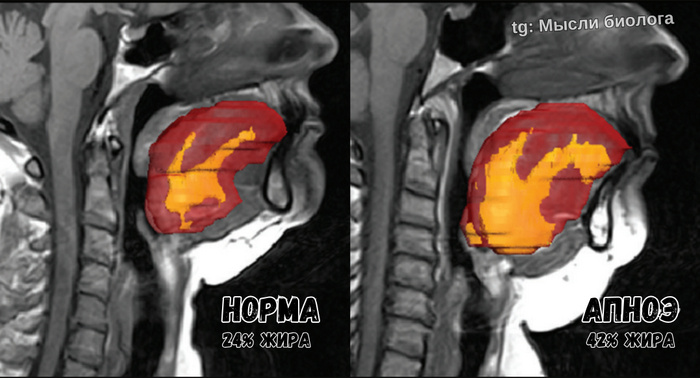

Почему из-за лишнего веса мы задыхаемся во сне

Наш организм умеет запасать жир не только на животе и боках, но и в тканях языка. А чем больше объём языка, тем выше риск того, что во сне он будет перекрывать дыхательные пути и приводить к апноэ.

На картинке с МРТ отлично видно разницу в уровне жира и размере языка, а также механику процесса.